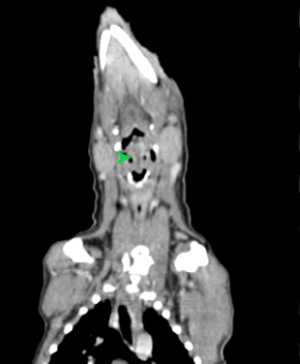

初步懷疑呼吸道阻塞,安排電腦斷層掃描/內視鏡探查手術,精準定位病灶團塊的範圍,

利用內視鏡輔助套環套住團塊後經電燒將可見到範圍盡量切除乾淨。

同時將切除的團塊做病理切片。術後三個月到現在沒有症狀也沒有復發。

病理報告為嚴重、慢性活躍性、漿細胞及化膿性喉炎,伴隨肉芽組織生成及局部上皮細胞異型性,會厭旁團塊